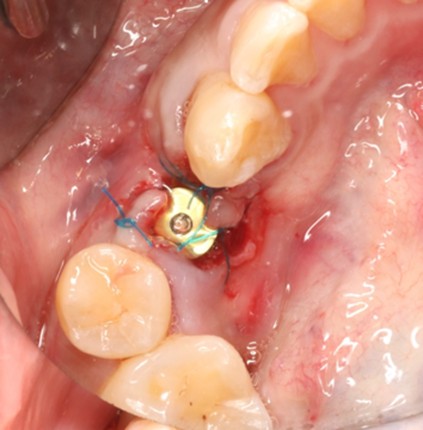

May 4, 2025: Extraction of the affected tooth.

Immediate implant placement (first-stage surgery) was performed right after tooth extraction.

Postoperative CT scans and intraoral photographs were obtained.